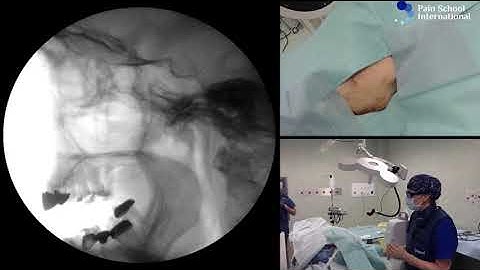

Gasserian ganglion Trigeminal block - made simplified by demo on the skull